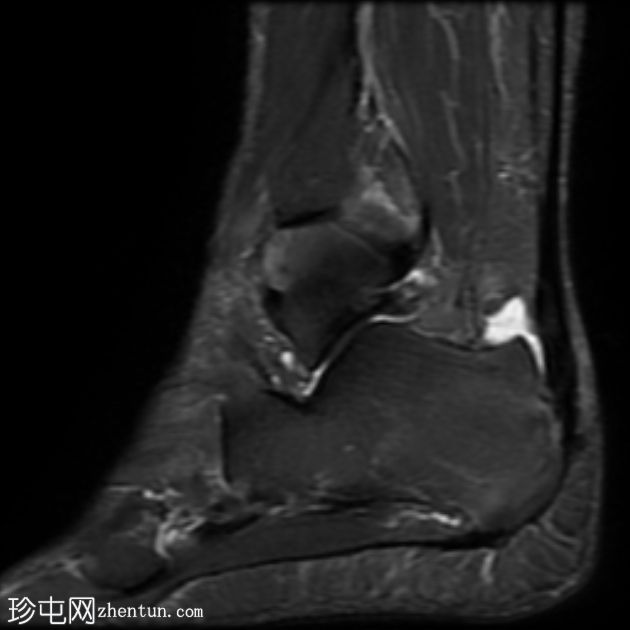

MRI

矢状位

T2

跟腱插入

,伴有跟腱明显增厚,可诱发异常信号、跟腱后滑囊炎、跟骨后突及骨髓水肿信号。

Haglund综合征的检查结果令人印象深刻。

Haglund综合征是指以下三联征(Haglund三联征):

跟腱插入性病

跟腱后滑囊炎

Haglund畸形(即跟骨后上外生骨疣)